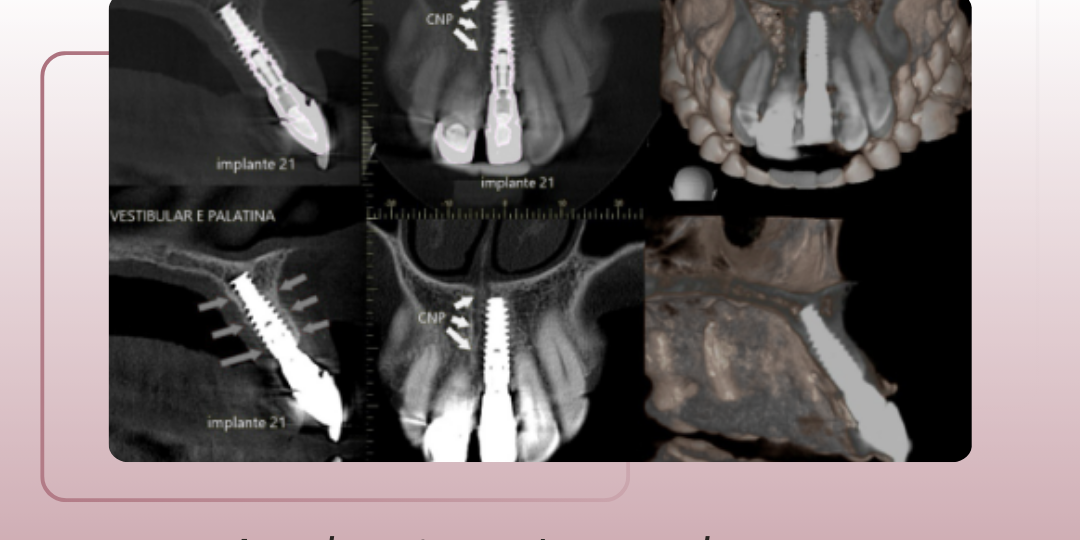

A estabilidade de um implante se constrói com acompanhamento, análise criteriosa e interpretação especializada dos exames de imagem – o papel do acompanhamento tomográfico.

Com a tomografia de alta resolução, é possível:

– Avaliar estruturas adjacentes como seios maxilares, canal mandibular e proximidade com raízes, prevenindo intercorrências;

– Detectar complicações como peri-implantite e reabsorções ósseas que comprometem a longevidade da reabilitação;

– Monitorar a estabilidade ao longo do tempo, observando posicionamento, adaptação óssea e sinais sutis de mobilidade;

– Planejar intervenções corretivas, como ajustes protéticos, reabordagens cirúrgicas ou enxertos — com base em dados objetivos e detalhados.

Na IRDO, entregamos mais do que imagens: oferecemos cortes direcionados, análise criteriosa e laudos que respeitam as nuances de cada fase do tratamento implantossuportado — da instalação à manutenção de longo prazo.